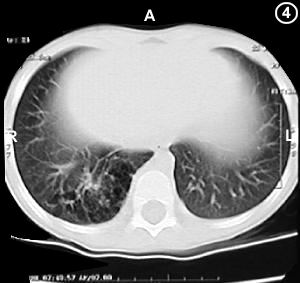

Corte Tomográfico " 4 "

Corte a nivel de la pase del tórax:

Parenquima pulmonar del segmento basal posterior del lóbulo inferior derecho no escapa de la malformación pulmonar.

Se confirma la localización de la enfermedad en todo el lóbulo inferior pulmonar derecho.